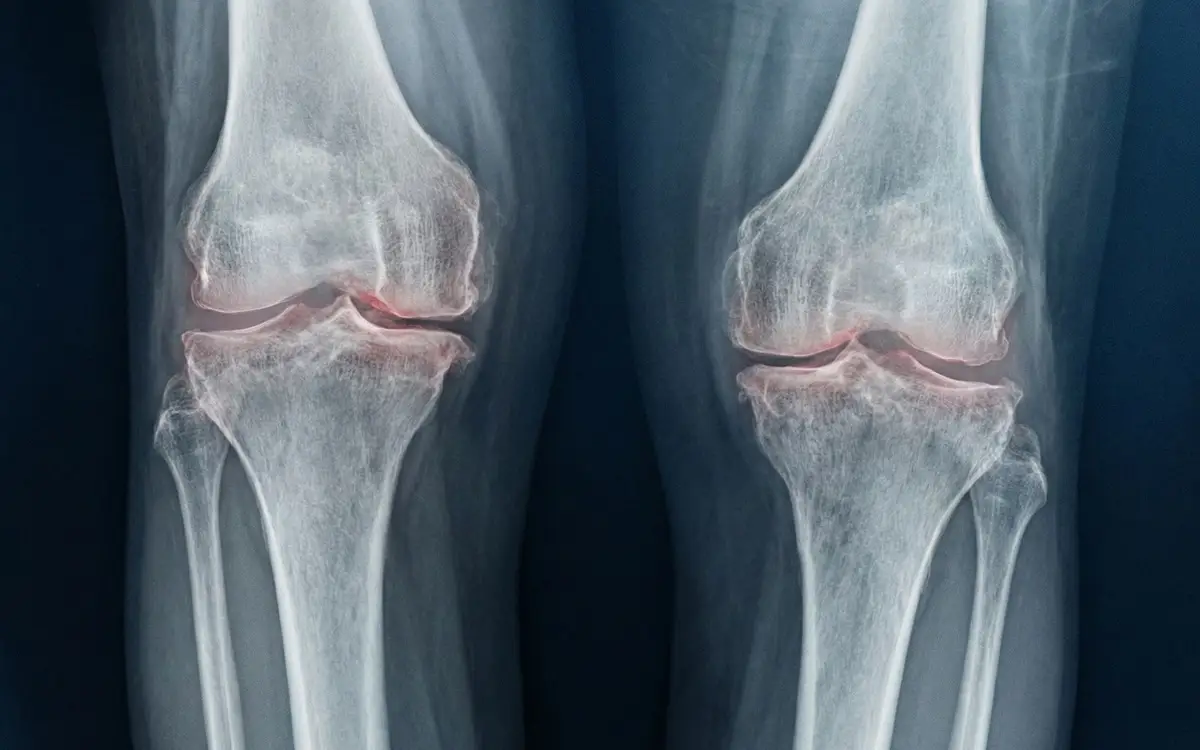

Descubre el impacto revolucionario de un medicamento innovador en el alivio de la osteoartritis".

Un Avance Prometedor en el Tratamiento de la Osteoartritis

La osteoartritis representa una de las principales causas de dolor y limitación funcional en individuos de edad avanzada. A lo largo del tiempo, los tratamientos convencionales han sido la principal opción para abordar esta afección…

El Impacto de un Nuevo Fármaco Experimental

Recientemente, se ha dado a conocer un importante avance en la investigación médica que podría revolucionar el tratamiento de la osteoartritis. Un fármaco en fase experimental ha mostrado resultados prometedores al regenerar las articulaciones afectadas y aliviar significativamente el dolor asociado con esta enfermedad…

Implicaciones para el Futuro de la Salud Articular

La posibilidad de contar con una terapia que no solo alivie el dolor, sino que también promueva la regeneración de las articulaciones dañadas, representa un hito crucial en la medicina. Este descubrimiento podría cambiar radicalmente la calidad de vida de millones de personas que sufren de osteoartritis en todo el mundo…

Avanzando hacia una Mejor Calidad de Vida

En resumen, el desarrollo de este fármaco experimental no solo brinda esperanza a quienes padecen osteoartritis, sino que también abre nuevas puertas en el campo de la medicina regenerativa. Con un enfoque centrado en la regeneración y alivio del dolor, se vislumbra un futuro prometedor para aquellos que enfrentan los desafíos de esta enfermedad degenerativa…